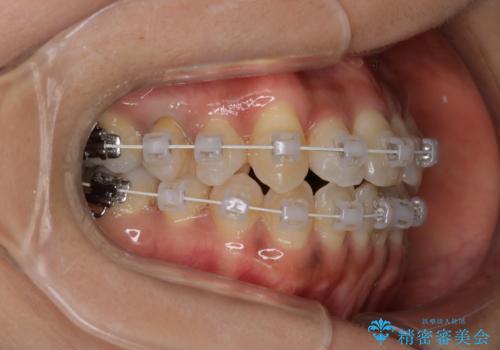

【審美装置】抜歯の本数最小限で行った矯正治療

- 治療計画

- 全体のがたつきを主訴に来院されました。4番目の歯を4本抜歯も検討しましたが、口元が下がりすぎてしまうリスクと2番目の転位うが著しく並べるのにかかる期間を考慮し、変則的な抜歯をし、並べる計画を立てました。

抜歯矯正のため2年はかかってしまいましたが、きれいに並び患者様にも満足頂きました。